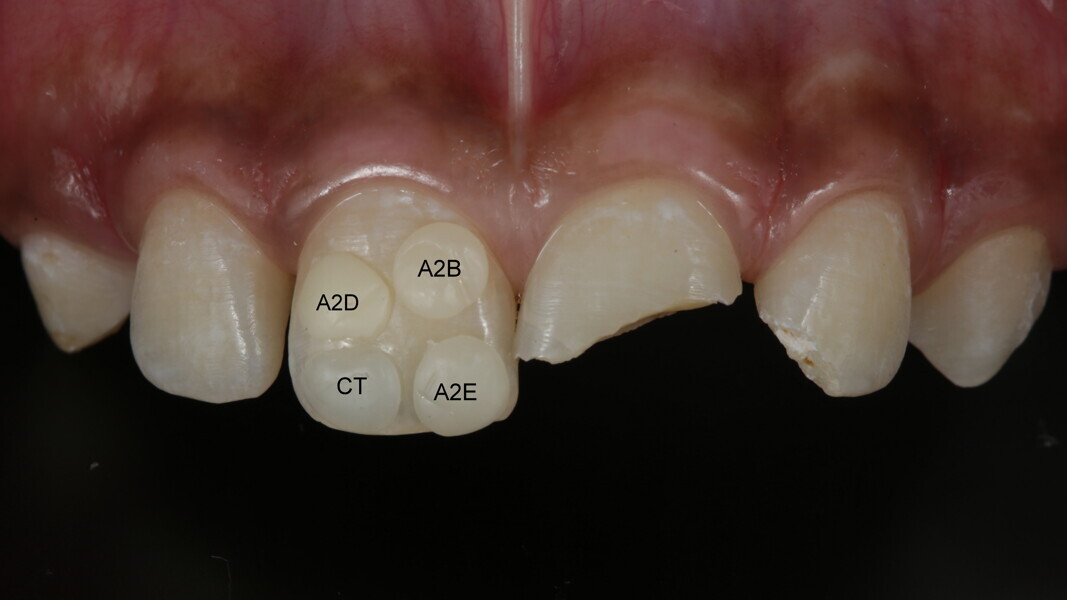

Vanini described an anatomical stratification technique that goes beyond the typical three dimensions (hue, chroma, value) of color. The technique, especially useful when esthetic demands are high, enables dentists to predictably create life-like esthetic restorations that are indistinguishable from natural teeth. [1, 2]

A 10-year-old male patient reported with a complaint of trauma to the upper left central and lateral incisors, involving the enamel and dentin. Direct composite was used in multi-layers and the smile was restored. This article explains detailed steps in the polychromatic layering technique with special emphasis on the finishing and polishing protocol. 3M Espe Filtex Z350 Xt was used with a universal bonding agent.

Fig 25-30: Layering protocol step by step